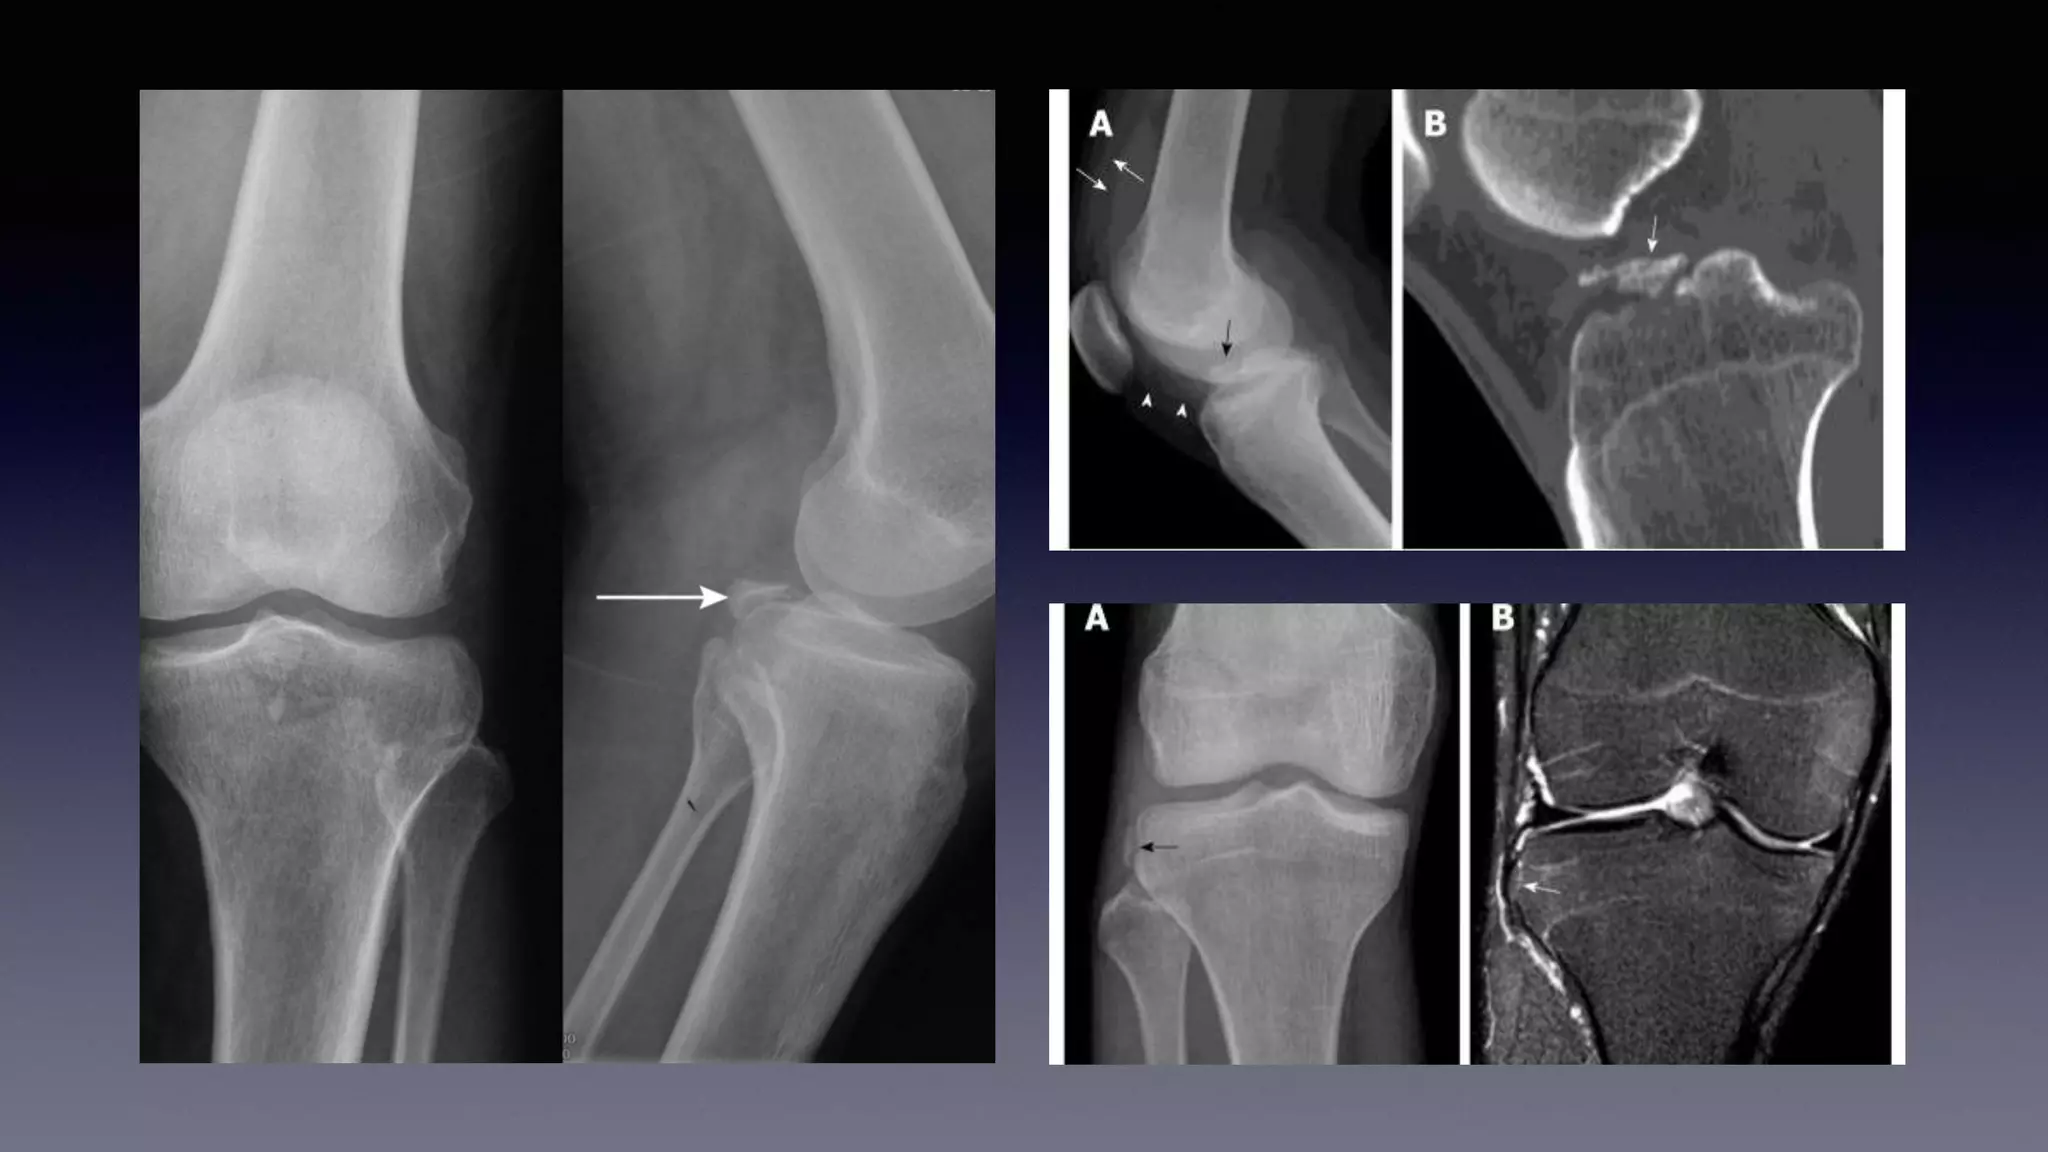

This document discusses using MRI to diagnose ligament injuries in the knee. It begins with an overview of MRI anatomy of the knee and expected pathology. It then discusses specific ligaments like the ACL, PCL, MCL and LCL. For the ACL, it shows images of acute tears, chronic tears and intrasubstance tears. It emphasizes knowing the knee anatomy well and correlating any abnormalities seen with clinical findings in order to apply the appropriate treatment.